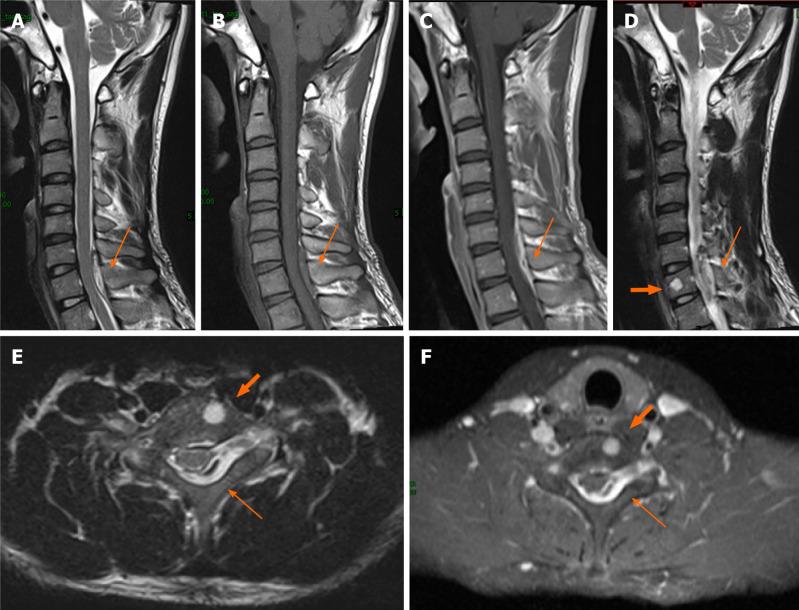

A 27-year-old man presented with acute-onset neck pain, numbness, and weakness in his extremities. Magnetic resonance imaging showed an epidural mass in the cervicothoracic (C6-T1) spinal canal and vertebral hemangioma (VH) involving the C7 vertebral body. C6-T1 Laminectomy and radical excision of the mass were performed. Histopathological examinations revealed papillary proliferation of vascular endothelial cells with thrombus formation, and an IPEH diagnosis was made. By his 6-mo follow-up appointment, his symptoms were relieved without recurrence. The possible pathogenesis, clinical and imaging features, differential diagnosis, and management of IPEH were reviewed.

一名27岁男性,出现急性颈部疼痛、肢体麻木和无力。磁共振成像显示颈胸段(C6-T1)椎管内有硬膜外肿块以及累及C7椎体的椎体血管瘤(VH)。实施了C6-T1椎板切除术并对肿块进行根治性切除。组织病理学检查显示血管内皮细胞呈乳头状增生并形成血栓,诊断为IPEH。到他6个月随访时,症状缓解且未复发。对IPEH的可能发病机制、临床和影像学特征、鉴别诊断及治疗进行了复习。